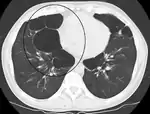

مقطع بالصدر بالتصوير الطبقي المحوري

حالة متقدمة من انتفاخ الرئة